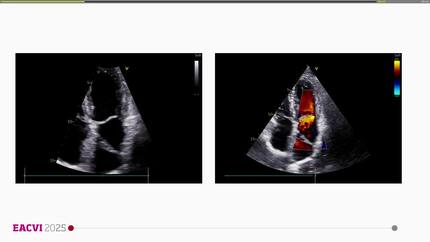

Shunting at intra-atrial level – benign or a mechanism for severe hypoxia?